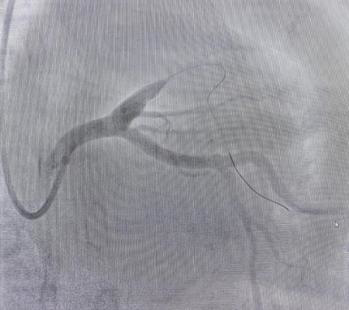

(导丝通过)

李绍波主任当机立断,将指引导丝送入分支。在普通导丝无法通过的情况下,转而使用CTO导丝,成功抵达对角支的远端。随后,依次运用小球囊、大球囊、切割球囊及药物球囊进行操作。在最大型号4.0的药物球囊完成血管扩张后,介入室内的人员均感到紧张情绪得以缓解。手术效果良好,患者的心率逐步稳定,呼吸困难的状况亦有所改善。